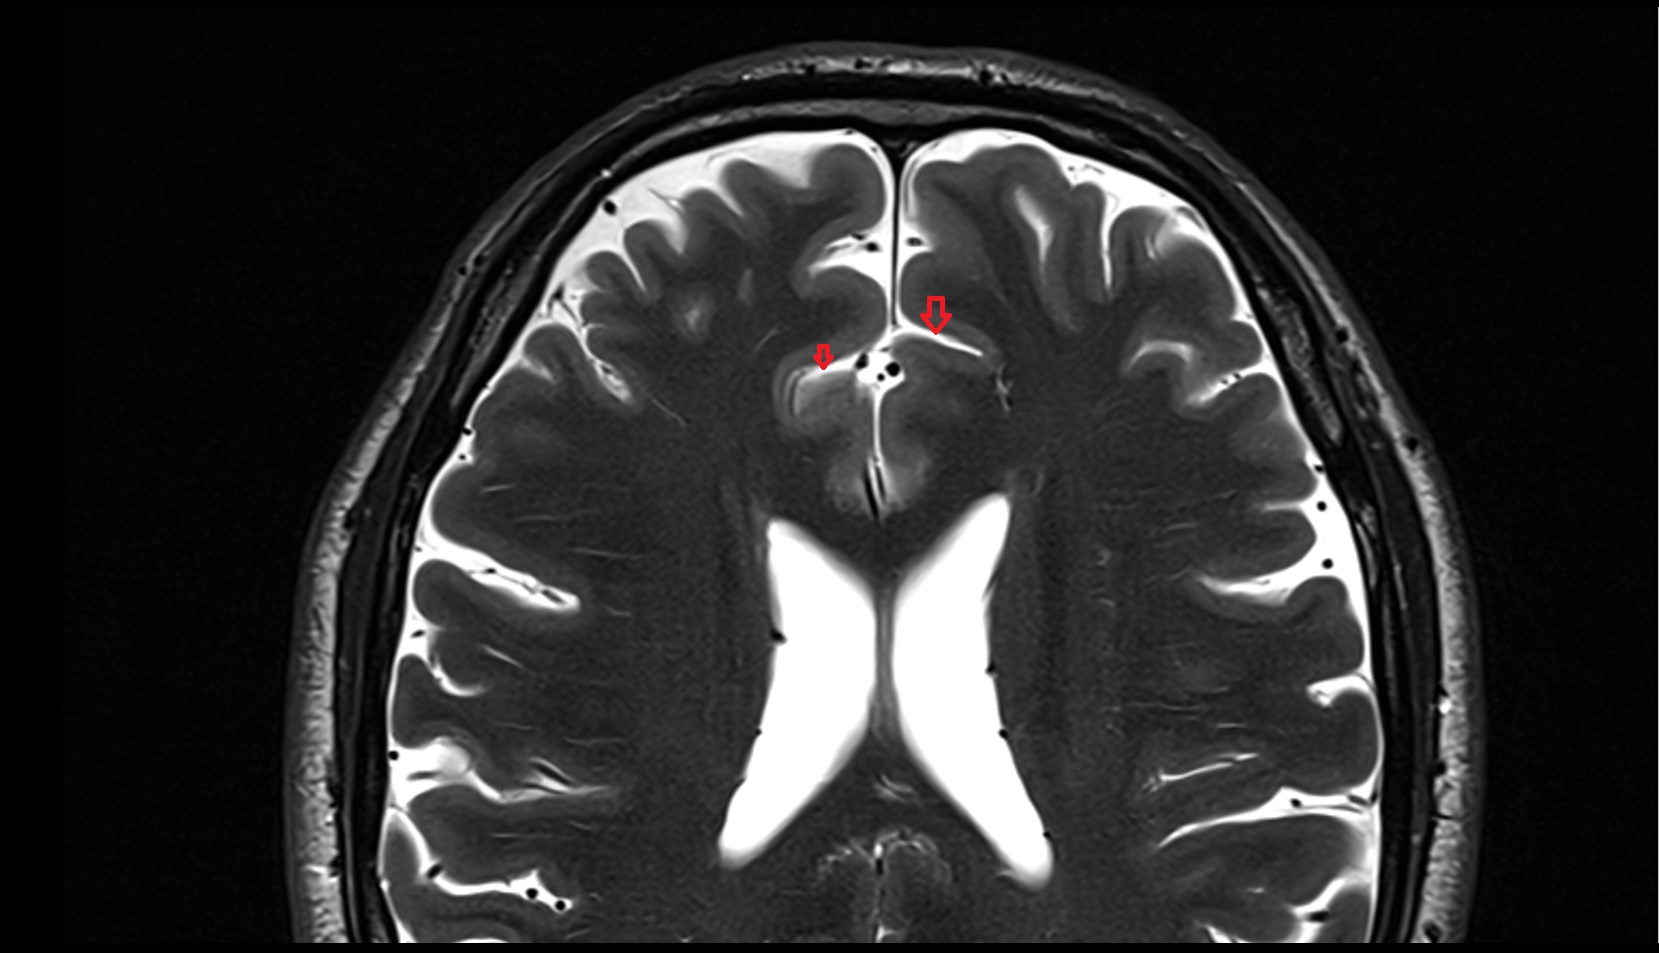

- Longitudinal cerebral fissure

- Central sulcus